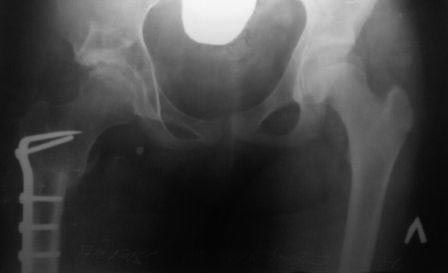

У нас реконструкция крыши делается по типу создание навеса (методика

УзНИИТО) в зависимости от недоразвития части крыши, ну чаще

передневерхней, сначала открываем сустав, ревизия, удаление

внутрисуставных тел, проверка хрящевой  губы, определение размера

недопокрытия головки,  дугообразная остеотомия крыши  по краю

прикрепления капсулы сустава к кости, параллельно стенки вертлужной

впадины до внутреннего кортикала , формируем крышу, после  устранение

торсии, вальгуса шейки и определяется размер укорочения, взятый

трансплантат внедряется в паз над крышей, примерно так.. То, что попало

в руки сейчас, примеры операции у пациентки 13лет, и результат у 12 лет,

до снимков не нашел, если найду еще отправлю.